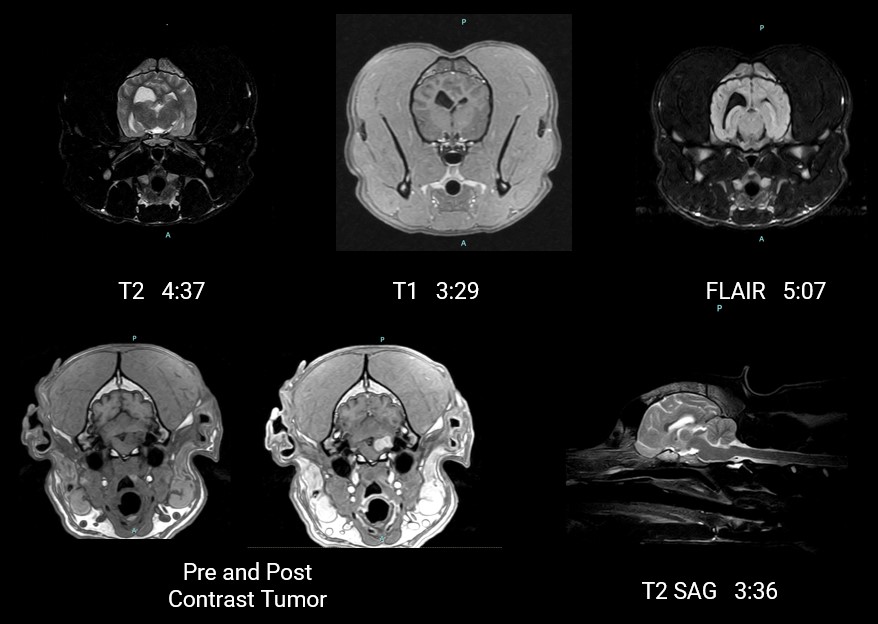

• DWI Diffusion Weighted Imaging water diffusion-based tissue characterization

• RF FatSat suppresses fat signal, enhancing soft tissue and pathology visualization

• IP-RECON iterative reconstruction delivers exceptional image quality with faster scan times